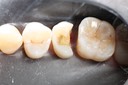

Gary Umeda #18-19 pre-op

Gary Umeda #18-19 pre-op 2